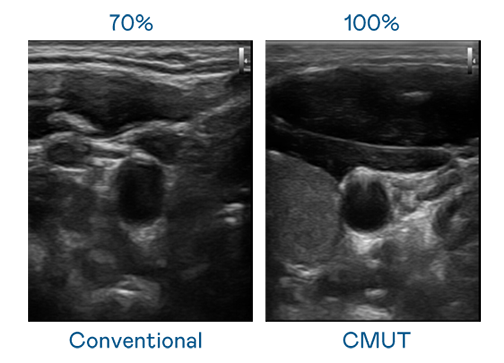

CMUT 技術是一種用電容式微機電元件來產生超音波訊號的技術。與傳統 PZT 壓電式技術相比,CMUT 頻寬增加 30%,更寬頻的超音波訊號讓影像解析度大幅提升,是實現高影像品質醫療超音波掃描、促進精準醫療發展的關鍵技術。

大頻寬帶來超清晰影像

超音波影像的解析度高低,首先取決於探頭能發出的訊號頻寬。AGGAME CMUT 可提供高清晰的超音波訊號,提供高頻寬、高靈敏度、影像紋理細節更高的超音波影像,協助醫護人員縮短影像判讀時間及利用精準的醫療影像進行診斷。